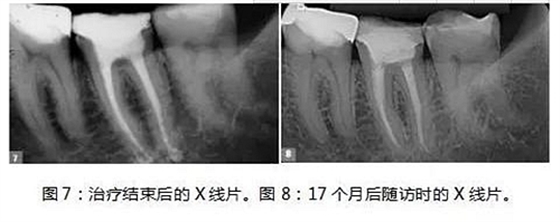

制備MTA-FILLAPEX糊劑并用主牙膠將其導(dǎo)入到根管內(nèi)(圖6)。使用攜熱器(Touch’n Heat, Kerr))除去過量的糊劑,熱垂直加壓。髓室用光固化復(fù)合樹脂密封,病人回到她的牙科醫(yī)生處,完成最終修復(fù)體的制作(圖7)。

17個月后,患者回訪, X線片結(jié)果顯示治療效果相當(dāng)成功(圖8),患者沒有陽性的癥狀和體征,牙齒的生理功能正常,根尖位置正常,根尖周多余的MTA-FILLAPEX已經(jīng)吸收干凈了。